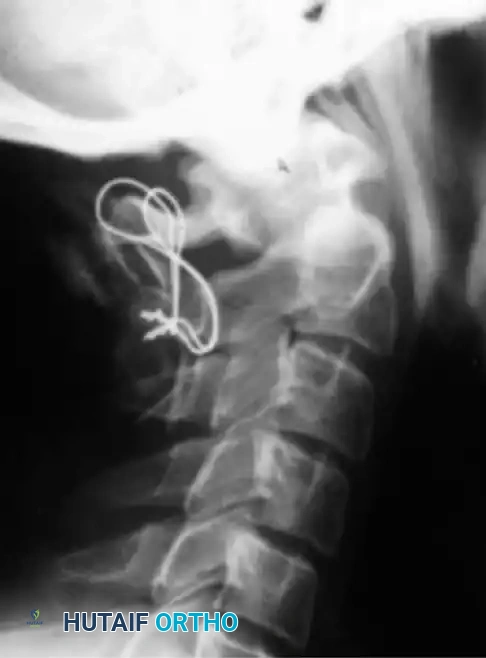

Anterior and Transoral Approaches

In rare instances, patients present with irreducible anterior spinal cord compression. This is typically caused by a fixed, posteriorly displaced os odontoideum or severe retrodental pannus that does not reduce with preoperative traction. In these cases, posterior fusion in situ is contraindicated as it would lock the spine in a stenotic state.

An anterior decompressive approach—specifically the Transoral-Transpharyngeal Approach—is required to resect the anterior arch of C1 and the compressive odontoid/ossicle, followed by a staged posterior stabilization.

Transoral Approach Steps:

1. Positioning and Retraction: The patient is positioned supine. A specialized transoral retractor (e.g